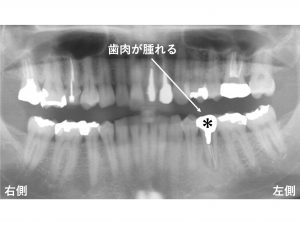

下顎左側の奥から3番目の歯の歯肉が腫れるとのことでした。

診査の結果、

この歯は歯根破折 していました。

この部分のみ拡大して見てみましょう。

*印の歯が今回問題となっている歯です。

歯根破折 しています。

抜歯が必要な状態です。